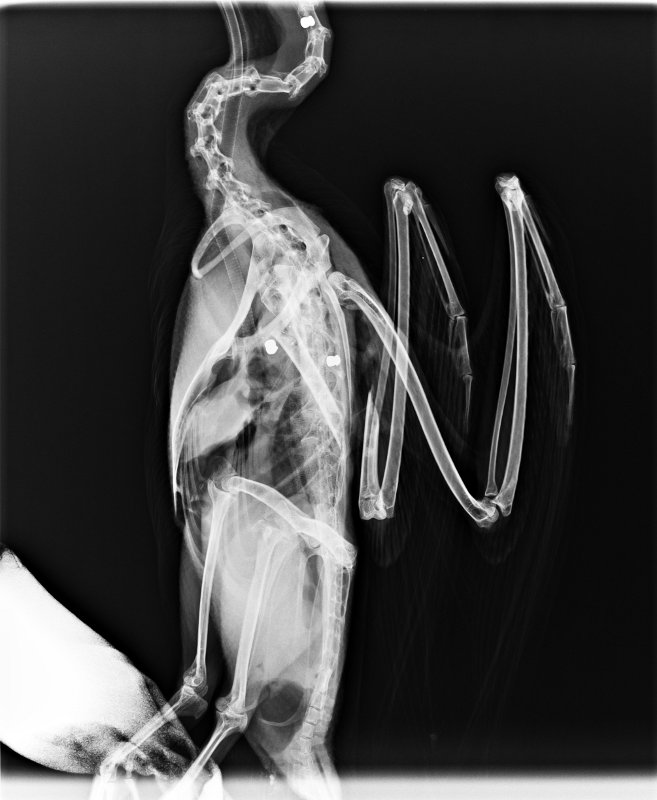

En esta ocasión el afectado fue un joven ejemplar de cormorán grande (Phalacrocorax carbo), el que fue víctima de tal atrocidad. En la primera exploración tan sólo pudo verse una fractura abierta de húmero, que había provocado una gran pérdida de sangre en el animal. Esto provocó que llegara al hospital en un estado de gran debilidad e hipotermia.

Debido al estado crítico del animal, se dejó el estudio radiográfico para el día siguiente, hasta conseguir estabilizarlo. Fue entonces cuando vimos el origen de tan fatal fractura, el ave estaba llena de perdigones. El destrozo provocado por los disparos era tan brutal y la fractura tan complicada, que nada pudo hacerse por salvar al animal.